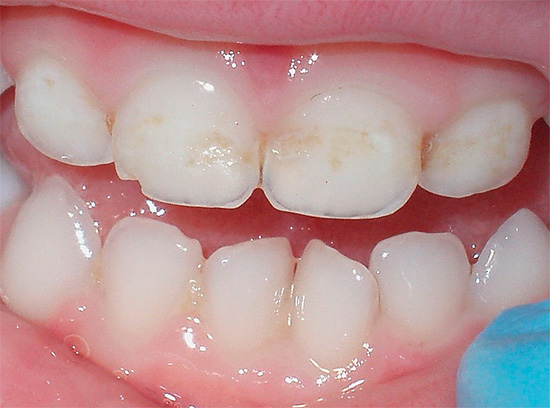

Oggi, a causa della popolarità della cura orale e della disponibilità di servizi dentali, la malattia è diventata meno comune, ma il problema è ancora rilevante nelle aree rurali e nei bambini in età scolare, quando quasi tutti i denti di un bambino sono affetti da carie (vedi l'esempio nella foto), e i genitori non sanno cosa fare in una situazione del genere.

- la presenza di lesioni in diverse fasi dello sviluppo - dalla carie iniziale "bianca" alla parodontite avanzata.

Oltre al fatto che la carie è pericolosa per la salute, provoca dolore e limita la scelta del cibo, è anche un grave problema estetico. La foto sotto mostra un esempio di carie generalizzata: